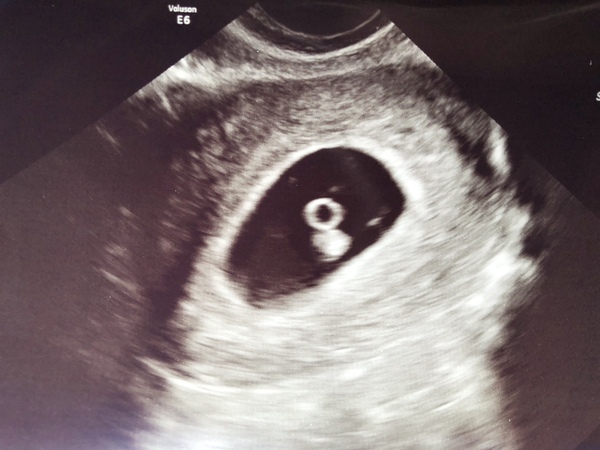

Just had my early scan - I’m a bit earlier than I thought (6+4) but all looks good so far! Amazing to see the heartbeat, I got a bit emotional about it Blush

@ronniemipperton amazing scan picture! Smile

@ronniemipperton congrats! Can't believe how much you can see on such an early scan. Stupid question to follow - is the round white circle just the head, or the whole thing?

@Egbeds not a stupid question at all, I had no idea what I was looking at until she explained - and I’m not sure I fully absorbed it but I think the round circle is the yolk sac and the foetus is the blobby bit underneath. I think the yolk sac starts shrinking once the baby has taken what it needs but it’s still pretty important at this stage.